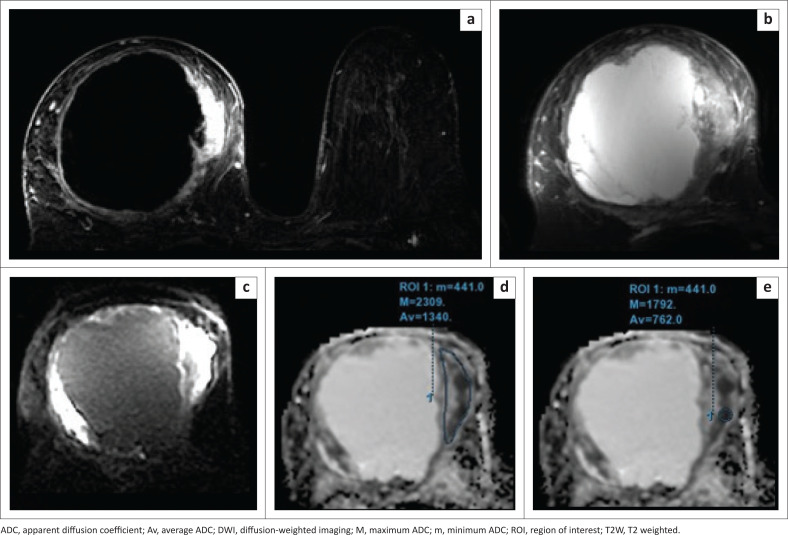

Method: Assessment of 38 breast lesions using DWI with a b value of 800 s/mm2, performed with 3 Tesla MRI. The diagnostic performance of two different region of Interest (ROI) placement approaches was compared to obtain a feasible cut-off value of apparent diffusion coefficient (ADC) to differentiate between malignant and benign lesions. The histopathological reports were used as the gold standard.

Results: ADC values of malignant lesions were significantly lower than those of benign lesions (0.84 × 10-3 mm2/s vs. 1.54 × 10-3 mm2/s). The average ADC measured using a small-sized 2D ROI including the darkest part in the ADC map, performed better than the large 2D ROI covering the entire lesion.